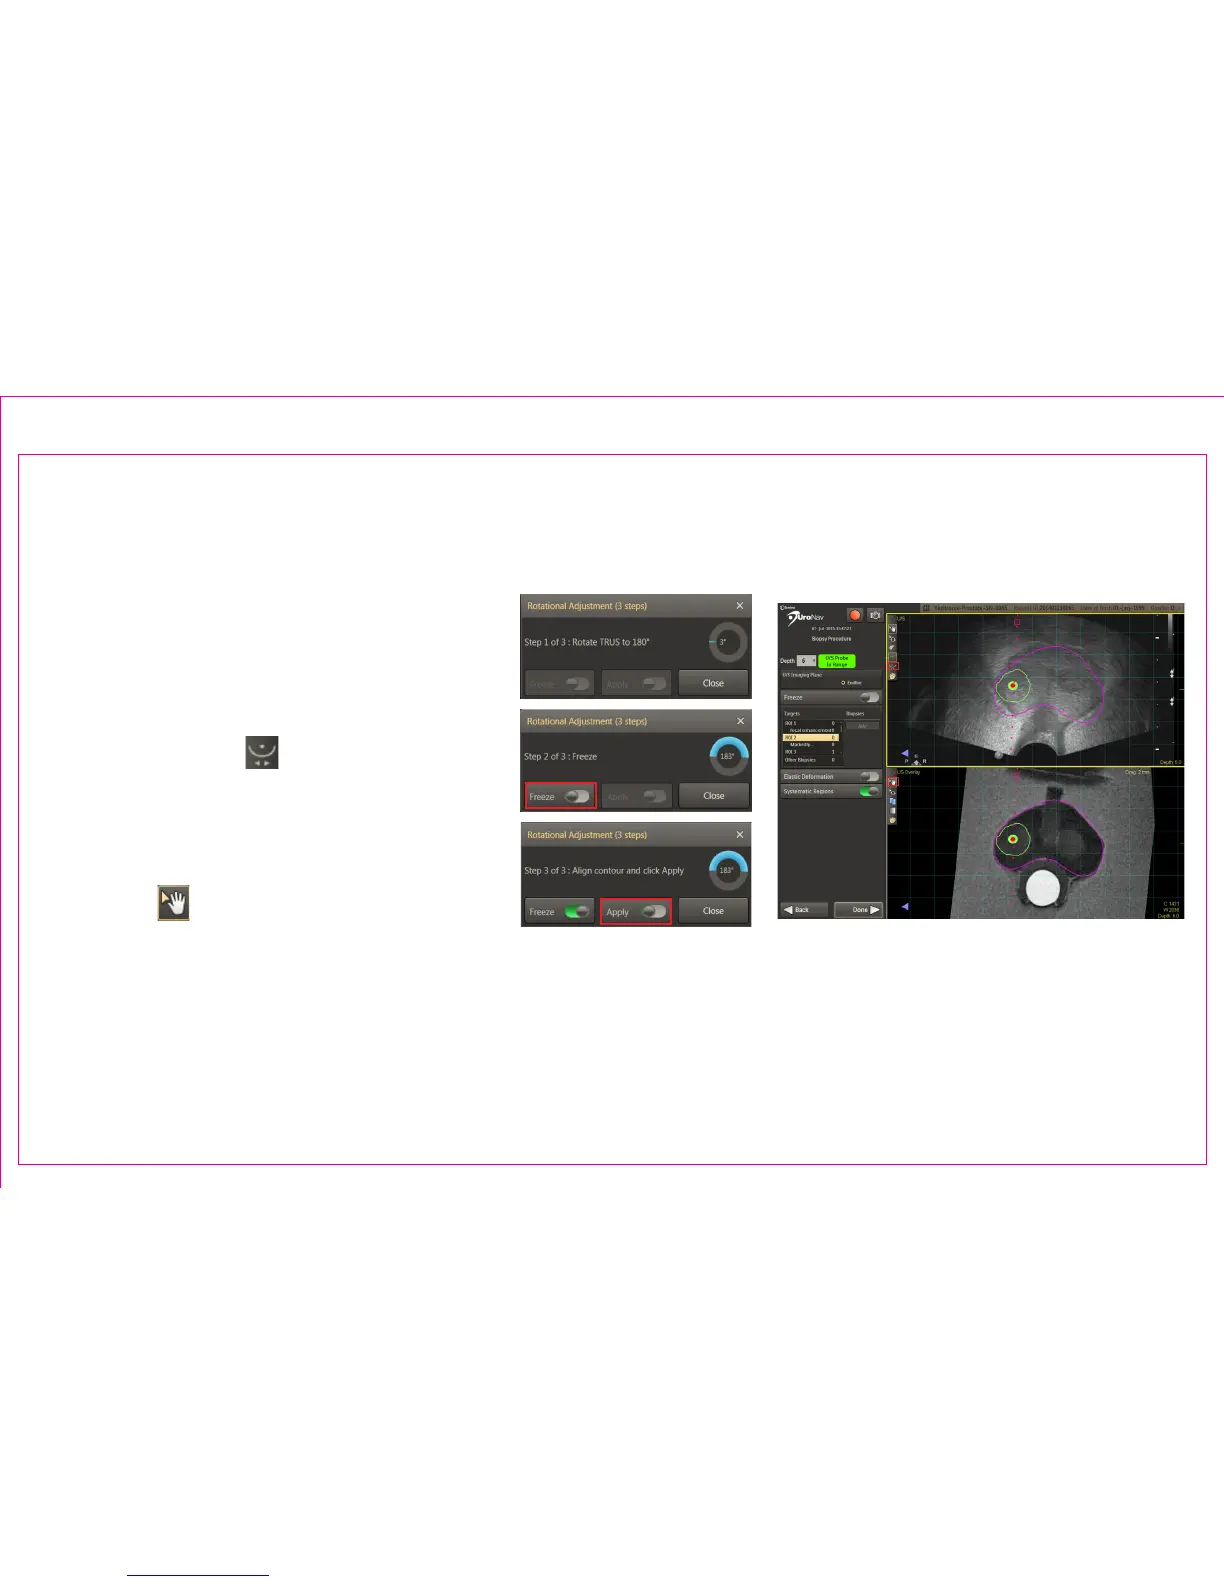

Fine tune the initial registration for possible

variances in the apex location after rotating

the probe 180° from the original sweep

orientation.

1. Select Rotational Adjustment icon in the

top left viewport

2. Follow screen prompts to rotate the

TRUS probe 180± 5° from original sweep

position

3. When indicated, press Freeze

4. Use Pan from the MR view (bottom

panel) to align the magenta contour

with the live, U/S view (top panel). Press

Apply.

Section 2.5: Biopsy Navigation – Rotational Adjustment